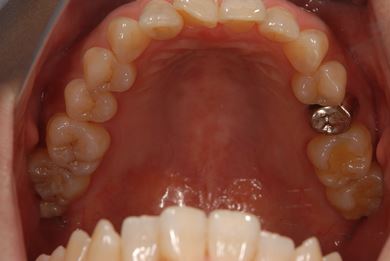

| 性別/年齢 | 女性 / 46歳 | ||||||||||||||||||||||||||||||||

| 主訴 | 左奥歯のインプラント治療を希望。 | ||||||||||||||||||||||||||||||||

| 治療方針 | 左下奥、欠損部分をインプラント治療にて、機能的・審美的回復を行う。 | ||||||||||||||||||||||||||||||||

| 治療内容 | インプラント2本、ハイブリッドセラミッククラウン2本 | ||||||||||||||||||||||||||||||||

| 総治療費 | 399,000円 | ||||||||||||||||||||||||||||||||

| 治療期間 | 5ヶ月 |